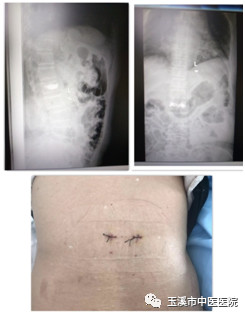

郭某某,女性,82歲,因“跌傷致腰背部疼痛伴活動受限3天”入院,入院腰椎MRI提示:腰1椎體壓縮性骨折(急性期),無手術(shù)禁忌癥,局麻下行PKP術(shù),手術(shù)歷時30min,出血5ml,術(shù)后患者自主翻身活動,次日下地行走活動,術(shù)后第三天出院。

術(shù)前影像資料

術(shù)中影像資料

術(shù)后影像資料